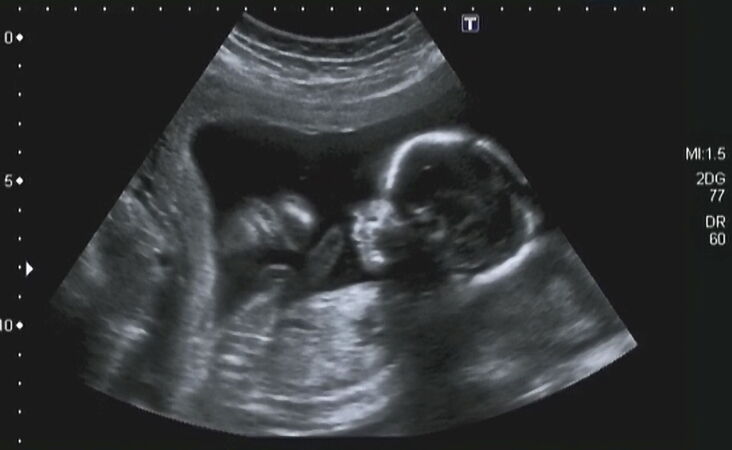

Hier gibt es keine Beratungsstellen wie in Deutschland. Abtreibung ist legal bis zur Geburt, genauer gesagt: grundlos bis zur 20. Schwangerschaftswoche, ohne Überweisung, ohne jegliche Hürden. Niemand fragt nach den Gründen oder: „Hast du dir das gut überlegt?“, „Wirst du von jemandem bedrängt?“, „Brauchst du Hilfe?“ Ab der 21. Woche (Anfang des 6. Monats) müssen zwei Mediziner die Spätabtreibung für gerechtfertigt halten und den „Eingriff“ genehmigen; die Vorschriften dazu sind sehr schwammig und lassen viel Raum für Interpretation. Die Abtreibungsrate ist sehr hoch. Hier wollte die Gründerin eine Alternative bieten, die den Frauen und Paaren liebevoll begegnet; vor knapp elf Jahren sind wir zum damals noch kleinen Team dazugestoßen.

Leider sind die Frauen hier in der Regel über Schwangerschaftsabbruch schlecht informiert; sie wissen nicht, was da körperlich und emotional auf sie zukommt. So hören wir nicht nur zu, nehmen den Druck weg und bieten praktische Hilfe an; ein wichtiger Teil unserer Arbeit ist, Information und Aufklärung über das Thema anzubieten. Ich (Rita) bin eine der Beraterinnen.